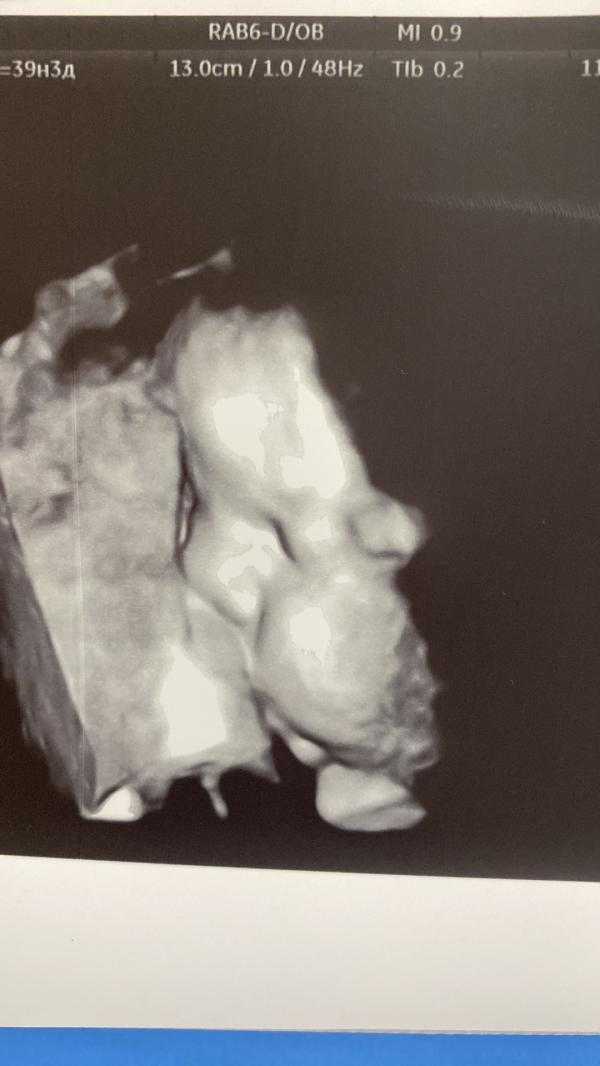

Девчуль!

А я родила) 🎇

Поехала вчера на консультацию , а мне сказали идите ка Вы с вещами сдаваться!

Очень тонкий рубец в 1 мм , ребёнок 39.4 доношенный полностью.

Так что…

Берегите себя и своих деток 🙌🏻

В ЖК местной мне сказали ходи до схваток 😰

И узи последние раз сделали на скрининге в 32 недели

Направление сама выпросила!

А я принимаю поздравления!

Девочка 👧🏼

3390 кг счастья 💫

49 см 😍

Такие пухленькие щечки 🥰

Жду встречи с ней уже…а пока буду восстанавливаться после КС

ВСЕМ ЛЮБВИ И ЗДОРОВЬЯ!